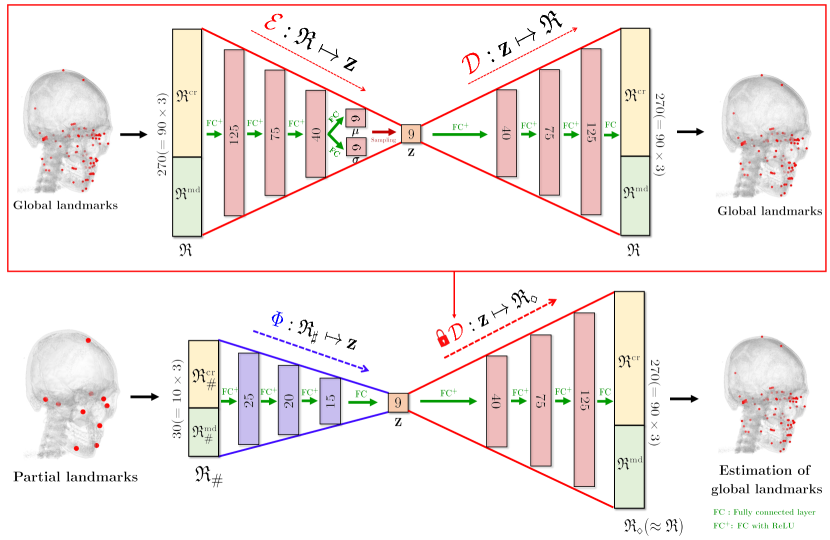

Using the landmark dataset , we aim to represent all landmarks in terms of -dimensional latent variables (with ) by learning an encoder and a decoder via the following energy minimization equation:

| (5) |

Here, and are the mean and standard deviation vectors obtained in the interim of the encoding process of an -th training data (i.e., ).

The encoder can be expressed in the following nondeterministic form:

where is a noise sampled from , is the Hadamard product (i.e., element-wise product), and vectors and are given by:

Here, the matrices represent fully-connected layers and ReLU is an element-wise activation function defined by . The decoder is the reverse process of the encoder , which can be represented by:

where the matrices represent fully-connected layers. The detailed network architecture is described in Figure 3.

After training the functions and , a nonlinear map is learned, which connects reference landmarks with a latent variable . It is achieved by the following energy minimization equation:

where can be obtained by the trained encoder and is a set of all functions that can be learned via the fully-connected network structure. The detailed architecture of the map is described in Figure 3.

The training of uses only the landmark dataset . Based on patterns learned from the landmark dataset, we are able to estimate all landmarks from the partial knowledge . By utilizing the given CT image data, therefore, we put a final touch on the rough estimation to achieve more accurate landmark placement.

2.3.2 Detection of cranial landmarks

Landmarks on the cranium that demonstrates rigidity have less variability between subjects. According to [Yun2020], cranial landmarks have smaller variance compared to mandibular landmarks with the normalization presented in Section 2.1. Moreover, our empirical experiment shown in Figure 6 demonstrates that the rough local-to-global estimation achieved using the VAE-based low dimensional representation provides more accurate annotations for cranial landmarks. Therefore, we again utilize a VAE-based low dimensional representation in the same manner as in Section 2.2 by using only the cranial landmarks . To increase the detection accuracy, we enrich the partial knowledge of by accurately detecting three additional cranial landmarks lying near the midsagittal plane (MxDML, Od, and PNS) based on the rough estimation . The overall process is illustrated in Figure 5.

Let be a concatenated positional vector with cranial reference landmarks and three finely detected landmarks obtained by . Using this partial knowledge , we find accurate cranial landmark positions via

| (15) |

where is a nonlinear map and is a decoder of VAE. Here, is a -dimensional latent variable given by and is an encoder of VAE. The maps and are trained in the same method presented in (5) and (10) using cranial landmarks . The detailed architectures of and are illustrated in Figure 5.

To conduct the initial local-to-global estimation explained in Section 2.2, 9-dimensional representation was used (i.e., and ). The VAE was trained using 45000 epochs, a full batch-size, and a learning rate. The nonlinear map was trained with 11000 epochs, a full batch-size, and a learning rate.

For each landmark, Figure 6 shows the performance evaluation achieved using 9 test data with respect to the averaged 3D point-to-point error. The mean detection error was 3.42 mm for the cranial landmarks (Figure 6(a)), 4.23 mm for the mandibular landmarks (Figure 6(b)), and 3.82 mm for all landmarks (Figure 6(c)). The error of the cranial landmark estimation was much smaller than that of the mandibular landmark estimation.